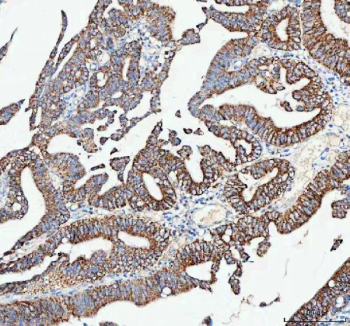

IHC analysis of CAMKK2 using anti-CAMKK2 antibody. CAMKK2 was detected in a paraffin-embedded section of human colorectal adenocarcinoma tissue. Heat mediated antigen retrieval was performed in EDTA buffer (pH 8.0, epitope retrieval solution). The tissue section was blocked with 10% goat serum. The tissue section was then incubated with 2 ug/ml rabbit anti-CAMKK2 antibody overnight at 4oC. Peroxidase Conjugated Goat Anti-rabbit IgG was used as secondary antibody and incubated for 30 minutes at 37oC. The tissue section was developed using an HRP secondary and DAB substrate.